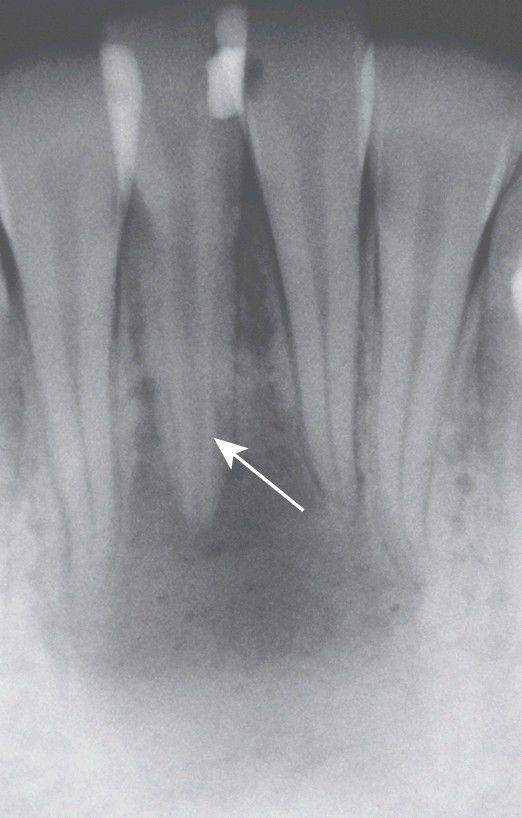

Periapical abscess with all four teeth nonresponsive to electric pulp testing. Decreased deposition of physiologic secondary dentin on the right central incisor (arrow) delineated the origin of the infection; endodontic treatment of this tooth resolved the lesion.